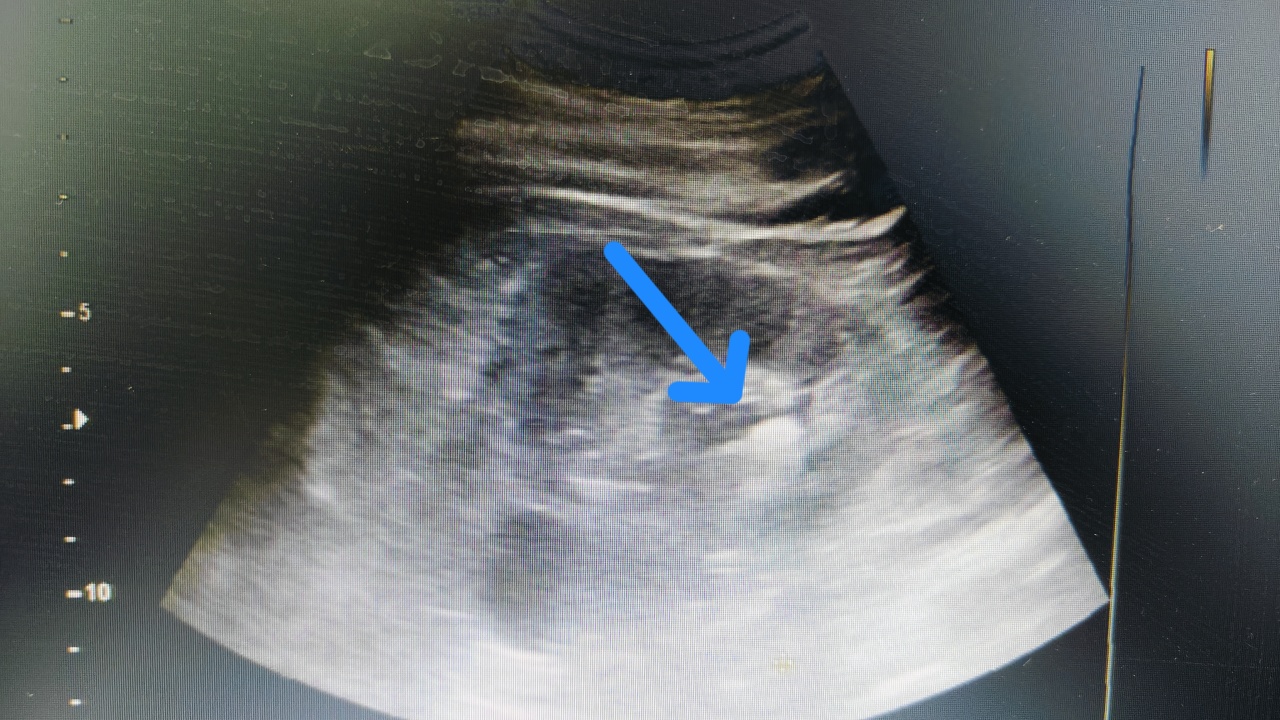

肾结石彩超就像给肾脏做一次“声波扫描”。医生拿着探头在你腰上滑来滑去,超声波就像“侦探的雷达”,遇到结石就会反射回来,在屏幕上形成亮闪闪的“小光团”——那就是结石“本石”啦!

结石在彩超下会“自带阴影”,就像妖怪现形时的黑雾,超好辨认!

如果结石堵住输尿管,彩超还能看到“肾积水”(肾脏被尿憋大了),就像水管堵了,水漫金山!